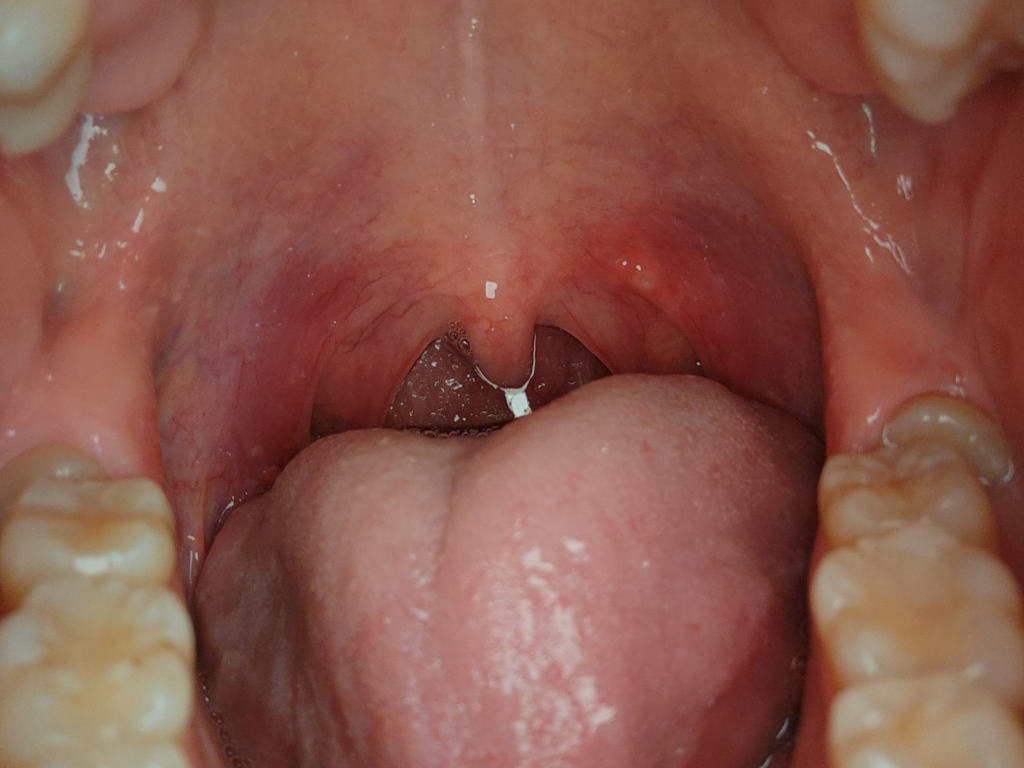

침 삼킬 때 오른쪽 목 통증 있는데 사진상으로 뭘까요

사진은 입 안 사진이고

목젖 옆 구내염같은 흰색 물집 보이고

이건 잘 안보이는데 오른쪽 편도에도 좀 큰 물집같은게 있는건지 모르겠어요ㅠㅠ

안녕하세요. 채홍석 의사입니다. 첨부해주신 사진상의 염증성 병변이 보이네요 코로나의 경우 증상으로 판단하는 것이 아니기 때문에 뭐라 드릴 말씀이 없네요.

보여주신 사진에 편도는 잘 관찰되지 않고, 말씀하신 궤양성 병변이 하나 보이는데 염증성 반응인지 덩이가 자라난 것인지 구분이 잘 되지 않는 병변이라 이비인후과 진찰을 받아보시는게 안전하겠습니다.

편도가 심하게 부어보이진 않습니다. 인후염 가능성이 있습니다.

말씀하신대로 좌측 병변은 구내염과 같은 궤양성 병변으로 보입니다.

아구창과 같은 바이러스나 세균에 의한 구내염으로 보입니다. 입 안에는 세균 감염 시에 지금과 같이 Aphthous ulcer 형태의 구내염을 보이는 경우가 많습니다